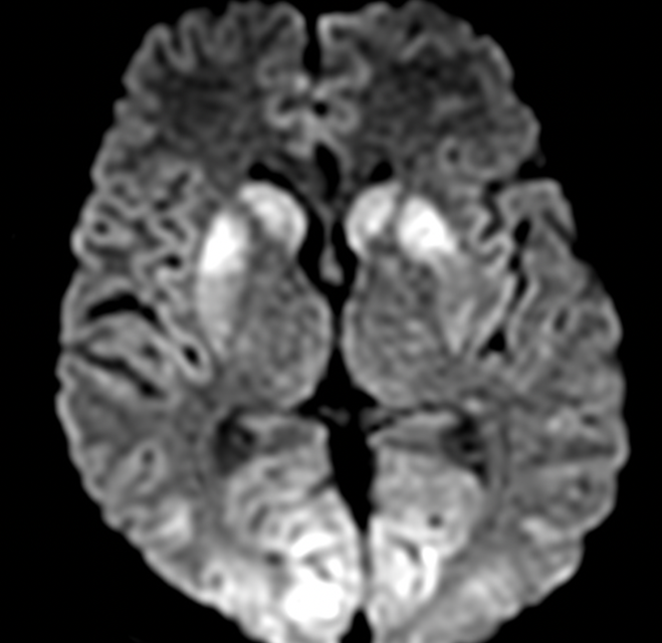

Caso clinico 4

Uomo di 47 anni trovato incosciente in casa. All’arrivo in PS: GCS 6, lattati elevati.

TC encefalo di base: negativa.

Perché il globo pallido bilateralmente è particolarmente vulnerabile nel danno da ipossia/monossido di carbonio?

- Maggiore permeabilità della barriera emato-encefalica

- Elevata densità di recettori glutammatergici

- Maggior contenuto di mielina

- Ridotta vascolarizzazione arteriosa

- Alto metabolismo ossidativo e vulnerabilità allo stress mitocondriale

Risposta corretta: E

COMMENTO

Il globo pallido rappresenta una delle strutture più sensibili all’ipossia e alla tossicità da monossido di carbonio per ragioni strettamente metaboliche.

Questa regione è caratterizzata da:

- elevata richiesta energetica

- intensa attività ossidativa mitocondriale

- dipendenza critica dalla fosforilazione ossidativa

Il monossido di carbonio esercita il suo effetto tossico attraverso:

- legame con la citocromo c ossidasi

- inibizione della catena di trasporto degli elettroni

- compromissione della produzione di ATP

Ne consegue un rapido fallimento energetico cellulare con sviluppo di edema citotossico, che si manifesta come restrizione della diffusione nelle sequenze DWI.

Dal punto di vista radiologico, il coinvolgimento simmetrico dei globi pallidi è altamente suggestivo di eziologia metabolico-tossica. La predominanza pallidale rispetto ad altre strutture dei nuclei della base è un elemento distintivo classico dell’intossicazione da monossido di carbonio.

Il pattern di distribuzione del danno è fondamentale per l’inquadramento eziologico:

- distribuzione simmetrica → suggerisce causa sistemica/metabolica

- selettività anatomica → riflette vulnerabilità bioenergetica regionale

- coinvolgimento prevalente del pallido → orienta verso tossicità da CO (rispetto ad altre encefalopatie ipossiche o tossiche)